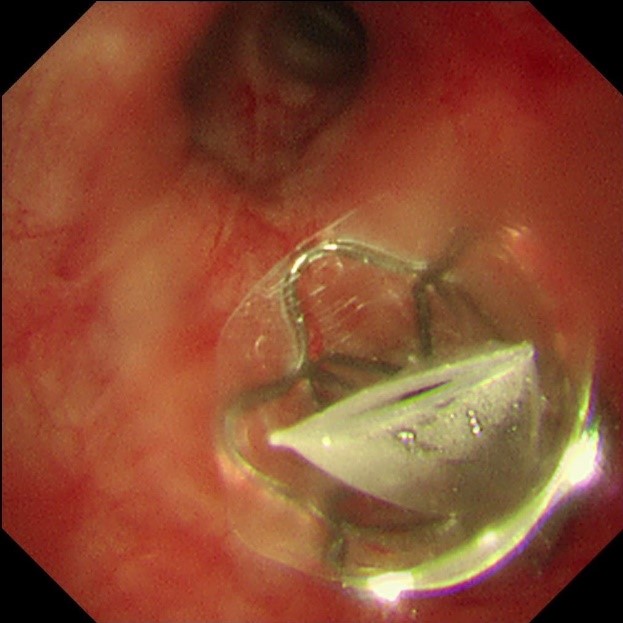

手术当天,蒋军红主任和曾大雄主任密切配合,用时30分钟便顺利完成手术。手术通过微创支气管镜介入,在高清内镜视野下,精准定位病变最严重的靶肺叶支气管,精准植入一枚微型支气管内活瓣(EBV-TS-5.5),术中实时验证活瓣开合状态良好,通气单向引流功能正常。

该技术的核心原理十分精妙:通过支气管镜将特制的微型单向活瓣,精准植入过度充气、丧失功能的病变肺叶支气管内,这个微型活瓣具备“只出不进”的独特功能——吸气时活瓣自动关闭,阻止外界气体进入病变废用肺叶;呼气时活瓣自动打开,让病变肺叶内残留的气体和分泌物顺利排出,从而促使靶肺组织逐渐萎陷、不张,达到肺减容的目的。

相比传统治疗,该技术具备创伤小、风险低、疗效确切、手术快捷等优势。全程经支气管镜介入,体表无切口、无出血,无需全麻气管插管,避免了传统肺减容手术的创伤,对高龄、体弱患者也能耐受。术前精准定位病变肺叶,术中精准植入活瓣,只针对无效病变区域治疗,最大程度保留健康肺组织,治疗针对性极强。单台手术操作时长通常30-60分钟,术后住院时间短,患者当天即可下床活动,快速回归正常生活。单向活瓣为可取出装置,若后续病情变化,可通过支气管镜再次调整或取出,无永久性肺组织损伤。